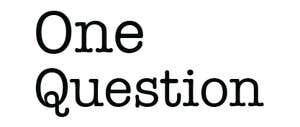

The Problem with the Mutation-Centric View of Cancer

How risk-assessments of cancer go wrong. -